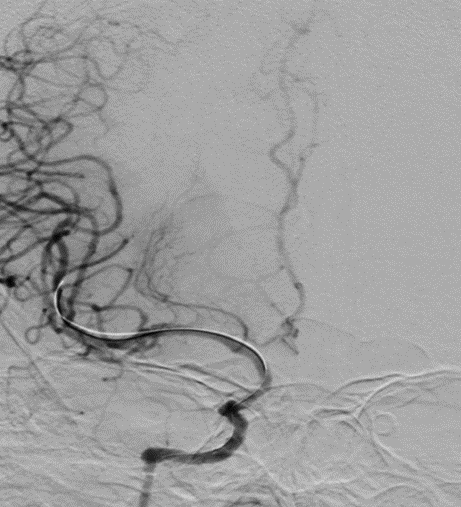

导丝怎么扩【载药时代 球扩天下】NOVA DES®颅内药物洗脱支架在颈内动脉颅内段重度狭窄的应用二例!_https://www.jmylbn.com_新闻资讯_第27张

DSA

重要影像结论:左侧颈内动脉C4段重度狭窄。